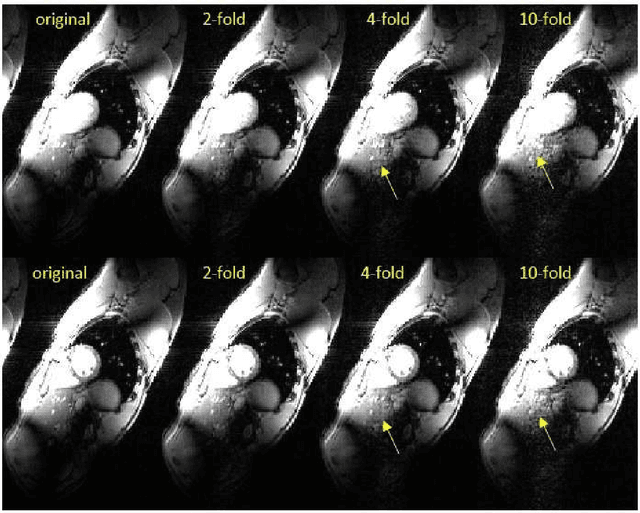

Abstract:Magnetic resonance imaging (MRI) nowadays serves as an important modality for diagnostic and therapeutic guidance in clinics. However, the {\it slow acquisition} process, the dynamic deformation of organs, as well as the need for {\it real-time} reconstruction, pose major challenges toward obtaining artifact-free images. To cope with these challenges, the present paper advocates a novel subspace learning framework that permeates benefits from parallel factor (PARAFAC) decomposition of tensors (multiway data) to low-rank modeling of temporal sequence of images. Treating images as multiway data arrays, the novel method preserves spatial structures and unravels the latent correlations across various dimensions by means of the tensor subspace. Leveraging the spatio-temporal correlation of images, Tykhonov regularization is adopted as a rank surrogate for a least-squares optimization program. Alteranating majorization minimization is adopted to develop online algorithms that recursively procure the reconstruction upon arrival of a new undersampled $k$-space frame. The developed algorithms are {\it provably convergent} and highly {\it parallelizable} with lightweight FFT tasks per iteration. To further accelerate the acquisition process, randomized subsampling policies are devised that leverage intermediate estimates of the tensor subspace, offered by the online scheme, to {\it randomly} acquire {\it informative} $k$-space samples. In a nutshell, the novel approach enables tracking motion dynamics under low acquisition rates `on the fly.' GPU-based tests with real {\it in vivo} MRI datasets of cardiac cine images corroborate the merits of the novel approach relative to state-of-the-art alternatives.